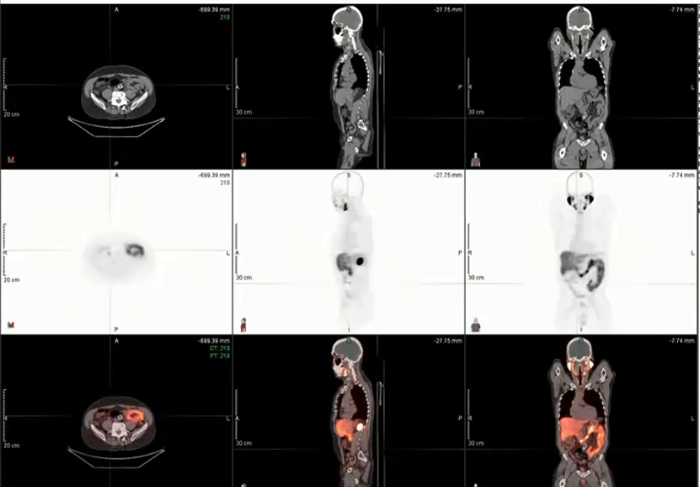

urethral tumor, urothelial carcinoma, PET, CT, palliative treatment, mediastinal nodes, biopsy, prostate gland, PSMA, false positive, pelvis with nodes, bone lesions, PSA, bladder